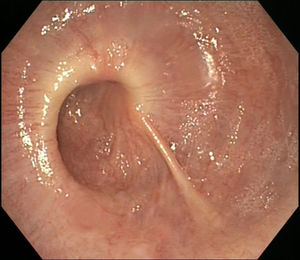

A 75-year-old man was referred due to dysphagia with each meal, weight loss of 5 kg and non-acidic regurgitation over the past 20 years (Eckardt score of 7/12). On upper gastrointestinal endoscopy, the oesophagus showed a striking spiral morphology with gastro-oesophageal junction spasticity (Fig. 1). An oesophagogram revealed a “corkscrew” image (Fig. 2). High-resolution manometry (HRM) showed elevated mean integrated relaxation pressure (46 mmHg; normal <15) and aperistalsis with pan-pressurisation every time the patient swallowed, consistent with type 2 achalasia (Fig. 3).1 Peroral endoscopic myotomy (POEM) was performed, revealing posterior myotomy measuring 12 cm in the oesophageal branch and 2 cm in the gastric branch, in 120 min, with no adverse events, although the procedure was technically complex due to the tortuosity and spasticity of the patient's oesophagus. Three months later, the patient showed significant improvement of both his signs and symptoms (Eckardt score of 1/12) and his oesophagogram and HRM findings.

Corkscrew oesophagus is a radiological term that alludes to the shape of the barium column in the distal oesophagus, classically associated with distal oesophageal spasm and, rarely, with achalasia.2 POEM is a treatment option that requires suitable prior planning given the morphological and functional characteristics of the oesophagus.